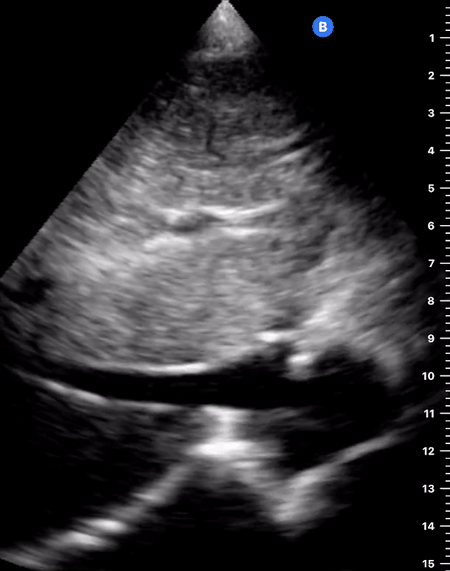

E-POINT SEPTAL SEPARATION

Active movement of the MV anterior leaflet during diastole, so it nearly touches the septum, correlates with good LV filling and ejection fraction. This can be assessed objectively by measuring the E-point septal separation (EPSS), which is the distance between the septum and the mitral anterior leaflet either in B-mode or M-mode. EPSS < 7mm is considered normal. EPSS is a good surrogate measure of ejection fraction, but it should be used with caution, as septal hypertrophy and mitral valve stenosis can lead to wrong estimations. In the PLAX view, it is important to have the septum lying horizontally flat on the image, as an oblique orientation may result in an overestimation of the EPSS.

Depiction of E-point septal separation: M-mode is used to measure the distance between the open mitral valve and the ventricular septum. Measurements greater than 7 mm are suggestive of depressed systolic ejection. (1. RV free wall, 2. Interventricular septum, 3. Mitral valve, 4. LV free wall). From: The "5Es" of emergency physician-performed focused cardiac ultrasound (11).